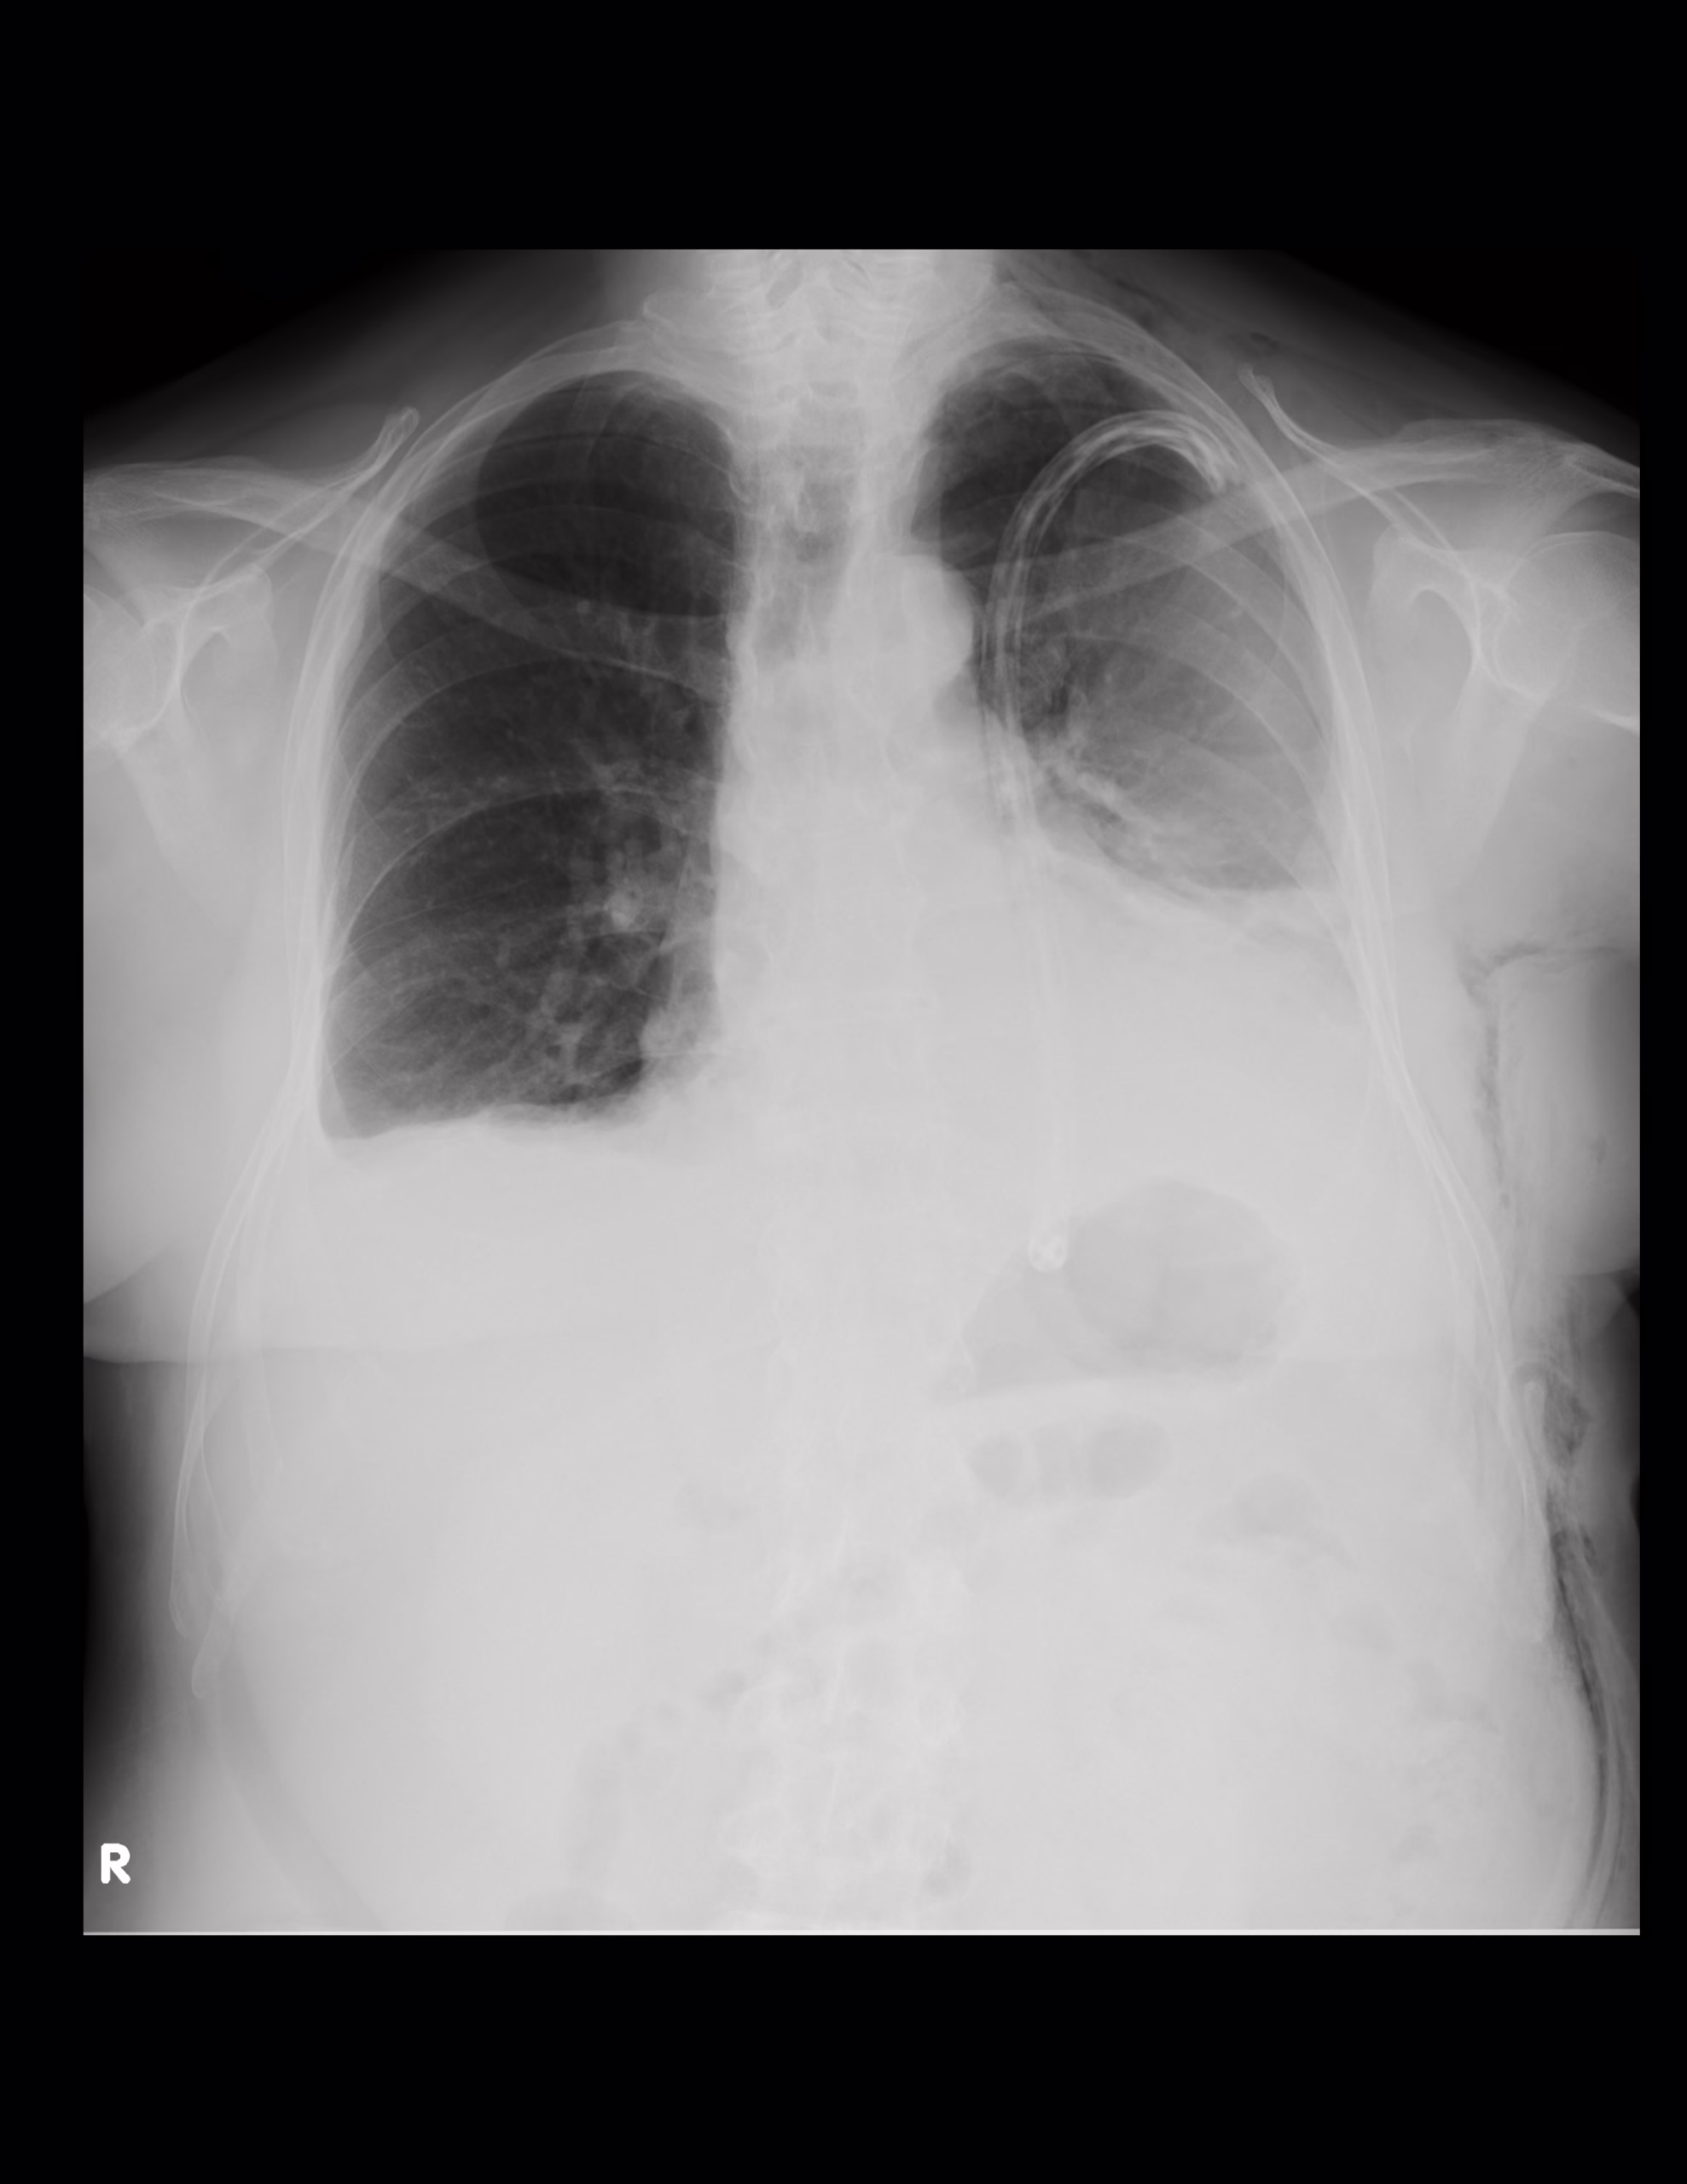

Imágenes radiolúcidas en los tejidos blandos en la región lateral y superior del hemitórax izquierdo, pared lateral del tórax y abdomen que se extiende a la región axilar en relación con enfisema subcutáneo.

Las estructuras óseas muestran una densidad conservada, hipoplasia del primer arco costal derecho en forma comparativa, cambios osteodegenerativos a nivel vertebral manifestado por osteofitos.

Opacidad en el hemitórax izquierdo haciendo signo de silueta con el contorno cardiaco, identificamos broncograma aéreo en la región parahiliar, obliteración del ángulo costodiafragmático lo que sugiere engrosamiento y/o derrame pleural, sonda torácica proyectada en el hemitórax izquierdo cuya punta se localiza en la porción superior.

Obliteración de los ángulos cardiofrénico y costodiafragmático del hemitórax derecho con infiltrado intersticial basal con tendencia a la consolidación observándose imágenes lineales radiolúcidas en la base pulmonar que sugieren broncograma aéreo.

IMPRESIÓN DIAGNOSTICA:

Enfisema subcutáneo en los tejidos blandos a la porción lateral izquierda del cuello, tórax y abdomen.

Hipoplasia del primer arco costal derecho, cambios osteodegenerativos a nivel vertebral manifestado por osteofitos.

Opacidad en el hemitórax izquierdo haciendo signo de silueta con el contorno cardiaco, el mediastino se observa central lo que sugiere doble componente de derrame y atelectasia, identificamos broncograma aéreo en la región parahiliar, obliteración del ángulo costodiafragmático lo que sugiere engrosamiento y/o derrame pleural, sonda torácica proyectada en el hemitórax izquierdo cuya punta se localiza en la porción superior.

Obliteración de los ángulos cardiofrénico y costodiafragmático del hemitórax derecho con infiltrado intersticial basal con tendencia a la consolidación con imágenes lineales radiolúcidas que sugieren broncograma aéreo.